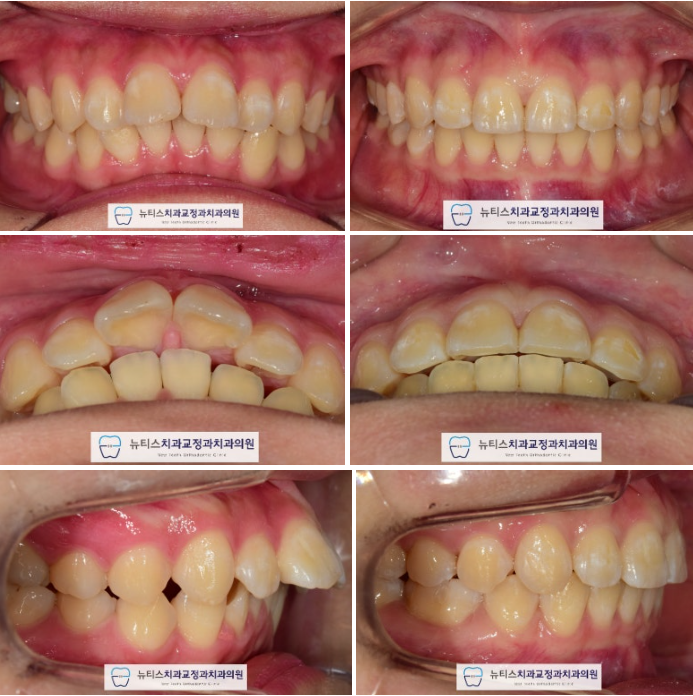

Æ¢¾î³ª¿Â ¾Õ´Ï

Ʋ¾îÁø Ä¡¾Æ

¸ÂÁö ¾Ê´Â ±³ÇÕ

»Ì¾Æ¾ßµÇ´Â Ä¡¾Æ

µîÀ» °í·ÁÇÏ¿©

À§¿¡´Â ½âÀº Ä¡¾Æ 2°³¸¦,

¾Æ·¡ÂÊ¿¡´Â ÀÛÀº ¾î±Ý´Ï 2°³¸¦ ¹ßÄ¡Çϱâ·Î ÇÏ¿´½À´Ï´Ù.

±³Á¤ ¿Ï·á ÈÄ »çÁøÀÔ´Ï´Ù.

°¡Áö·±ÇÑ Ä¡¿À» º¸À̸ç

±³ÇÕ°ü°è°¡ Åé´Ï ¹°¸®µíÀÌ Çü¼ºµÇ¾ú½À´Ï´Ù.

ÀÓÇöõÆ® ´ë½Å À̸¦ »ÌÀº °ø°£À» ÀÌ¿ëÇÏ¿©

µ¹ÃâµÈ ¾Õ´Ï¿Í »ß¶ÔÇÑ Ä¡¾Æ¸¦ °¡Áö·±ÇÏ°Ô ¸¸µé¾ú½À´Ï´Ù.